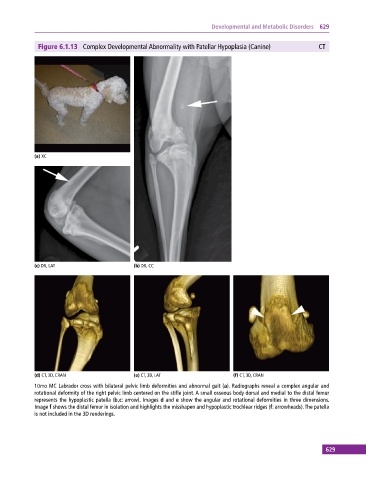

Figure 6.1.13 Complex Developmental Abnormality with Patellar Hypoplasia (Canine) CT

10mo MC Labrador cross with bilateral pelvic limb deformities and abnormal gait (a). Radiographs reveal a complex angular and

rotational deformity of the right pelvic limb centered on the stifle joint. A small osseous body dorsal and medial to the distal femur

represents the hypoplastic patella (b,c: arrow). Images d and e show the angular and rotational deformities in three dimensions.

Image f shows the distal femur in isolation and highlights the misshapen and hypoplastic trochlear ridges (f: arrowheads). The patella

is not included in the 3D renderings.